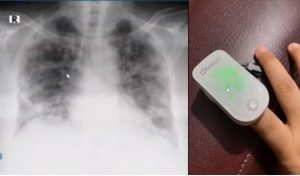

” Satu jiwa diselamatkan maka seolah-olah menyelamatkan seluruh jiwa manusia, betapa bernilainya jiwa manusia (Waman ahhyaa fakaannama dalam surah almaidah ayat 32). Maka jangan pernah bosan untuk melakukan protokol kesehatan jaga keluarga 1 aja nyawanya selamat . Covid itu khas, menyerang bagian basel kanan dan kiri makanya harus cek saturasi oksigen. Harus dalam posisi diatas 95 (98-99%), jangan dibawah angka tersebut, jangan sampai terlambat karena ini tidak dapat tertolong .

- Apabila ada riwayat penyakit paru,harus diperiksa layak dan tidak layak, sebab ada beberapa bagian yang sakit parunya biasa, ada yang tidak biasa.